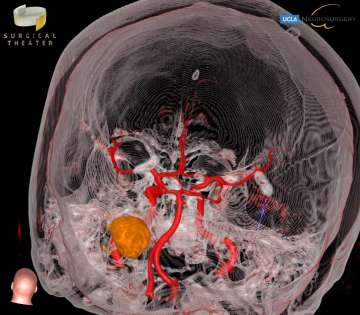

Choroid plexus tumors arise from the choroid plexus within the ventricles of the brain. These tumors are rare, representing only about 3% of brain tumors in children. About 10-20% of brain tumors found in the first year of life are choroid plexus tumors. The majority of choroid plexus tumors are either choroid plexus papillomas (CPP) or choroid plexus carcinomas (CPC). CPPs are benign and far more common, accounting for 80-90% of choroid plexus tumors. CPCs are malignant, and are more likely to spread to other parts of the brain and spinal cord. Symptoms for these tumors include headaches, nausea, lethargy, irritability, problems with development, and enlarged fontanelles. All of these are a direct result of the increased intracranial pressure and of the hydrocephalus that may be caused by the tumor. Surgical resection is the mainstay of treatment, but can be particularly complex in these cases, and should be performed by an experienced pediatric neurosurgery team.